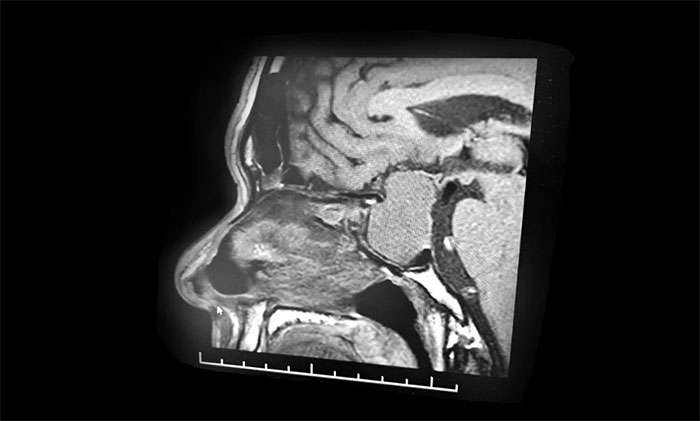

行鞍區(qū)磁共振增強(qiáng)提示:蝶鞍顯著擴(kuò)大,鞍區(qū)見(jiàn)一典型的“啞鈴”狀腫塊,大小約40*43*24mm。病變向鞍上生長(zhǎng),凸入鞍上池,推移視交叉;向下生長(zhǎng),鞍底受壓變薄、凹陷,蝶竇受壓;右側(cè)海綿竇可見(jiàn)包繞。

李士其教授、黎軍主任、潘仁龍主任組成的專家團(tuán)隊(duì)通過(guò)詳細(xì)了解病史和仔細(xì)閱片后,為患者認(rèn)真分析了目前的病情及手術(shù)風(fēng)險(xiǎn),并反復(fù)討論、仔細(xì)評(píng)估。從影像學(xué)資料上看,腫瘤呈“啞鈴”形,并且瘤體已經(jīng)非常大了,屬于巨大垂體瘤。瘤體占據(jù)鞍區(qū),并向蝶竇和鞍上發(fā)展,侵襲右側(cè)海綿竇,視神經(jīng)、視交叉受壓,所以需要馬上進(jìn)行手術(shù)切除,解除壓迫,若任其發(fā)展,患者將來(lái)有失明的風(fēng)險(xiǎn)。

▲ 巨大垂體瘤,呈“啞鈴”形